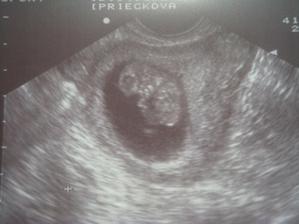

°°°°po zistení,že čakáme dvojčatká som bola úplne bez slov...na ďalšej kontrole bolo už však len jedno,to druhé malo "syndrom mizejíciho dvojčete",ale pevne verím,že ten náš prcek to zvládne a bude nám robiť radosť...po tých mojich pesimistických obavách som sa konečen dočkala...

°°°°15.1.som maminke krásne ukázalo,že mala zbytočné obavy,mám 3cm,som 10+1tt,pekne som zamávalo ručičkami,urobilo zopár kotrmelcov,aj keď maminke to moje divočenie sposobuje migrénu a nízky tlak,ale určite to zvládne...dievčatám so srpnoviek moc ďakujem za podporu 🙂 a tiež mojim dvom spriazneným dušiam 🙂